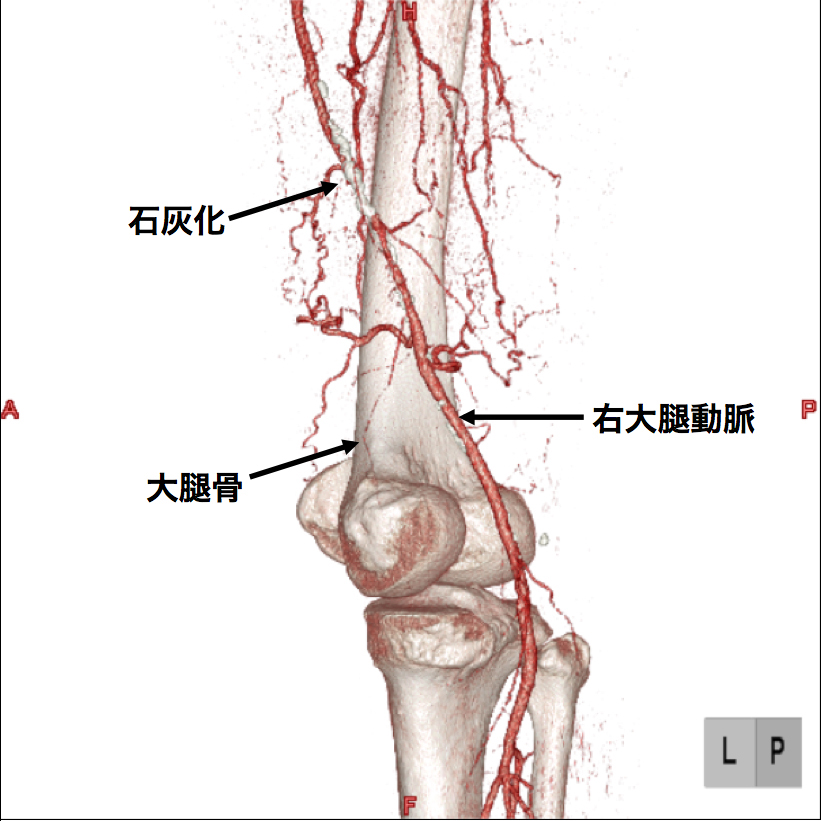

3、造影CT検査 造影剤を点滴しながらCTを撮像することで、血液の流れ、血管の状態などを把握します。情報量が多く治療方針を決定する場合に役立つので当院では特に力を入れている検査です。(図2、3、4)

【図2】下肢造影CT検査 この画像は血管の立体的な走行の把握に有用です。 右足大腿部の血管に強い石灰化(動脈硬化の変化)があります。